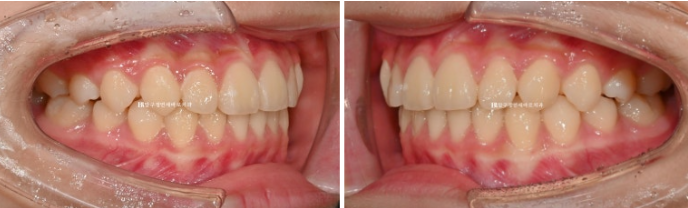

어금니 교합은 1급 교합관계를 보입니다.

2022.09~2024.09